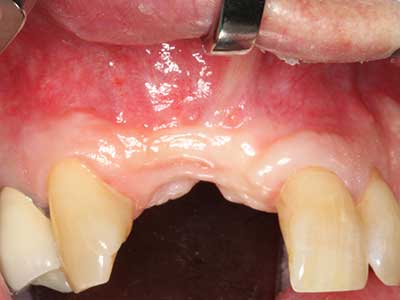

La piezochirurgia presenta altri vantaggi per quanto riguarda la raccolta di blocchi ossei. Oltre all'elevata precisione dell'osteotomia appena descritta, l'utilizzo di puntine per sega molto sottili permette di minimizzare in maniera significativa la perdita di materiale. È molto probabile che si verifichi una maggiore perdita di materiale durante la raccolta utilizzando puntine di strumenti più spessi, in particolare delle frese Lindemann (Lakshmiganthan, Gokulanathan et al. 2012). La separazione basale, necessaria in particolare per i trapianti di blocchi nella zona retromolare, viene semplificata grazie a seghe specificatamente progettate di forma rettangolare; di conseguenza la piezochirurgia è considerata una procedura precisa, semplice e sicura per la raccolta di blocchi di osso nella zona retromolare (Happe 2007) (figg. 1-12).